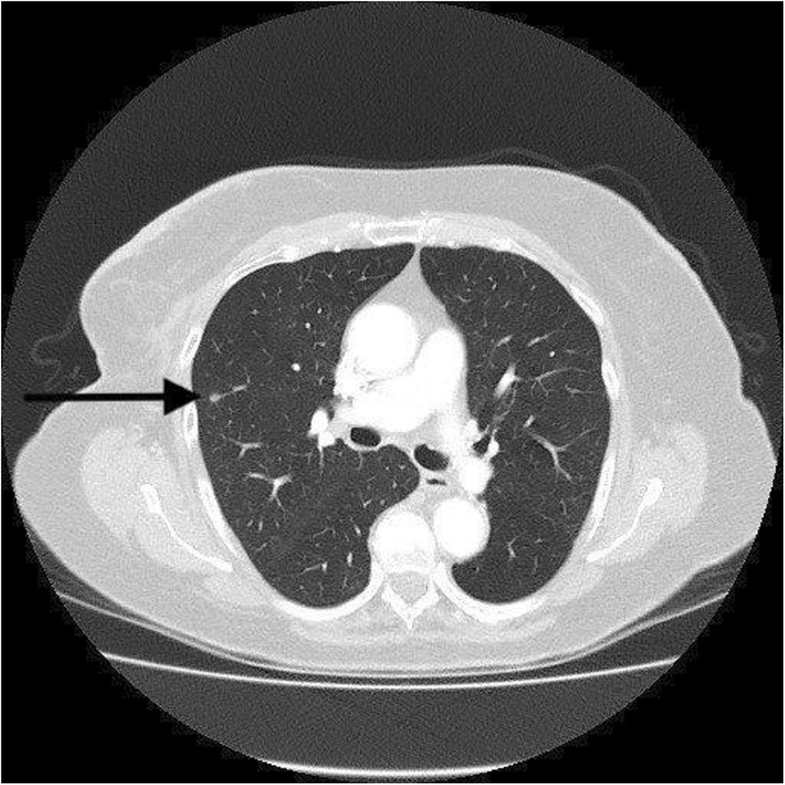

cT images of a 46-year-old patient with breast cancer ... from www.researchgate.net Nuclear) and show up on my ct scans as well. Ct scans can help doctors: The scan is painless and takes about 10 to 30 minutes. The specialized cone beam breast ct (cbbct) scanner, developed by boone and colleagues, uses the same amount of radiation as a conventional mammogram. I freaking out today though because i have a hard area in my left breast. Areas commonly scanned for cancer include the head, neck, chest, abdomen, pelvis, or limbs. My bone mets are checked using ct scans. Learn the stage of your cancer.

A critical review of the chest CT scans performed to ... from media.springernature.com Cas article google scholar 6. The value of preoperative staging chest computed tomography to detect asymptomatic lung and liver metastasis in patients with primary breast carcinoma. 234 views answered >2 years ago Several types of cancer can form in the breast, making it the second most common cancer that affects american women. The cancer develops when abnormal cells crowd out healthy ones, potentially causing a lump in the breast or a bloody discharge from the nipples. It is sometimes called computerized tomography or computerized axial tomography (cat). When the doctor knows this, they can choose the best course of treatment and maybe even predict your chances of recovery. A sentinel lymph node biopsy may first be performed to determine whether cancer has spread to the lymph glands under the arm.